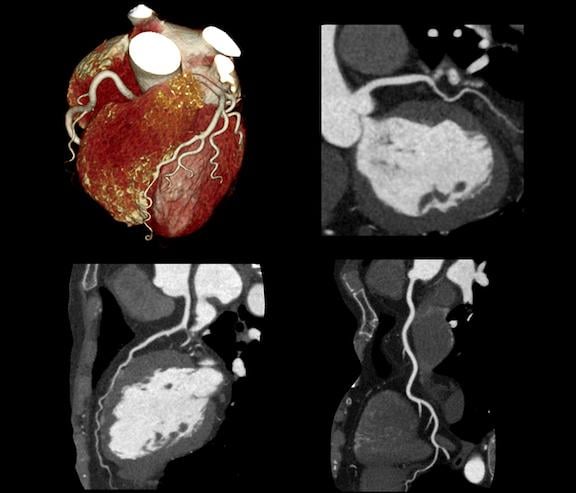

February 20, 2024 — Ultrahigh-spatial-resolution photon-counting detector CT improved assessment of coronary artery ...

July 14, 2021 — Performing the first cardiac scan on their new photon-counting detector computed tomography (CT) scanner ...